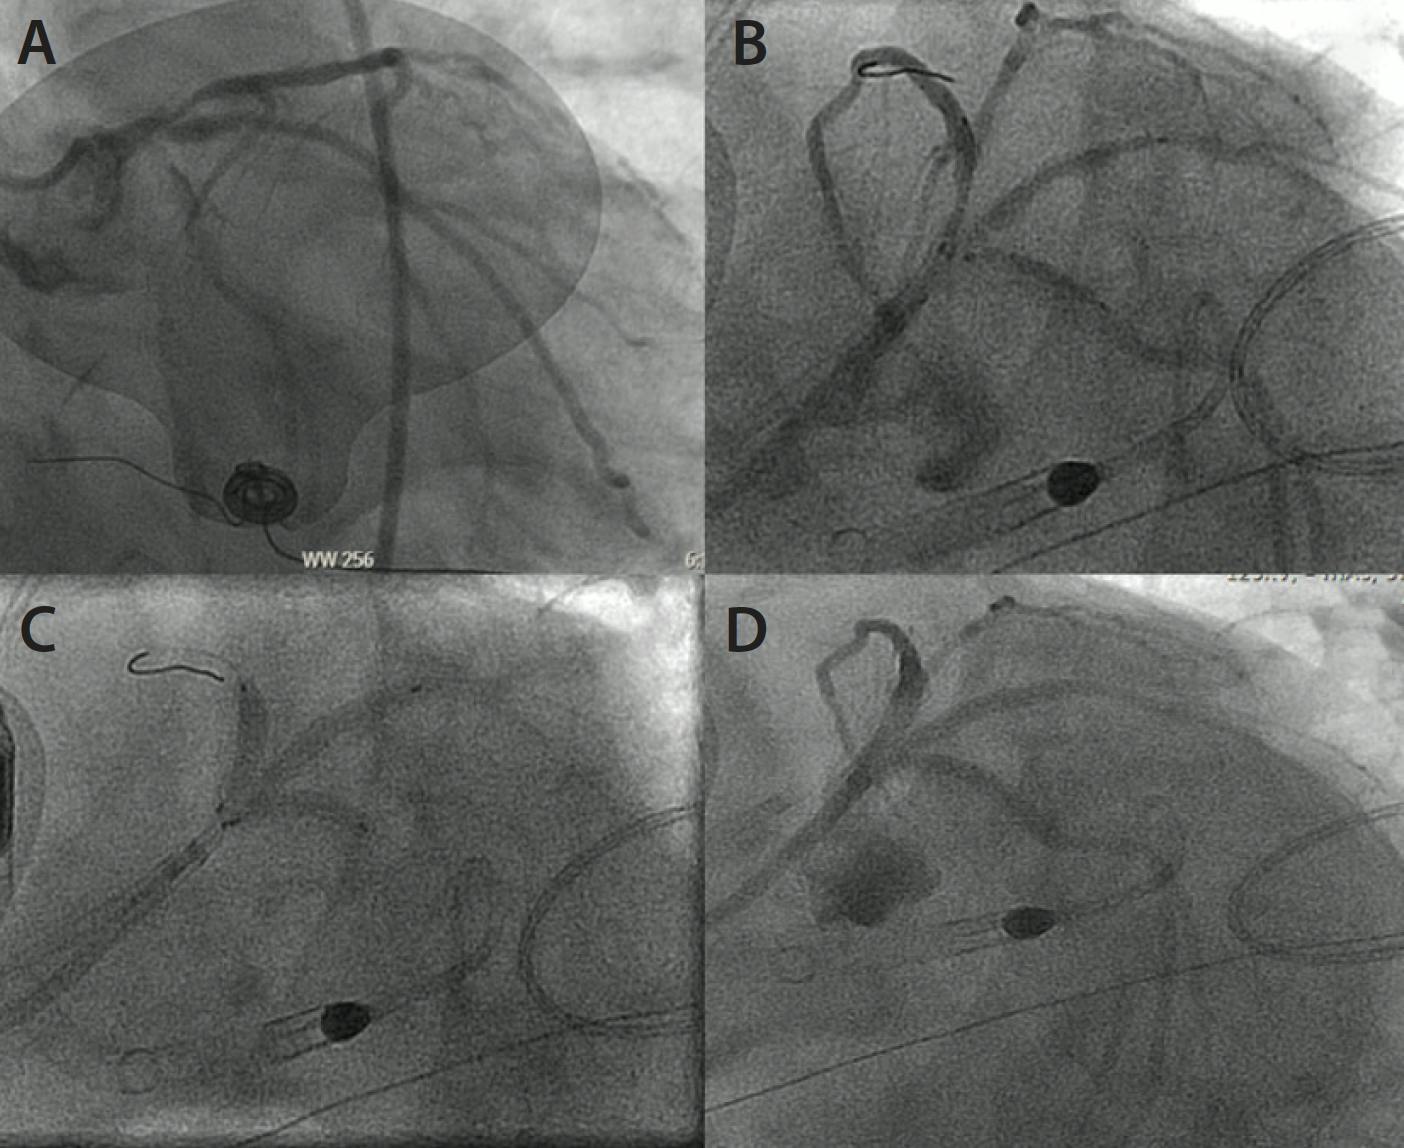

Additionally, from a pharmacology perspective, operators must consider the slower metabolism of drugs routinely administered for conscious sedation and the increased risk of a “paradoxical reaction” with the associated dangers of inadvertent gear removal at critical points during the procedure, and they must be mindful of the underlying theme of “start low and go slow.” During complex PCI in elderly patients, time on table is a limited resource, and operators should remember that improving efficiency through adequate preparation and planning, rapidly cycling through different strategies, and even pursuing investment procedures such as STAR (subintimal tracking and reentry) (Figure 2) when appropriate can help improve the safety of a case.

Figure 2. Octogenarian presenting with anterior STEMI due to acute left anterior descending artery occlusion (A). Flow restored after angioplasty (B) with resolution of angina and ST elevations; however, after stent deployment, a large diagonal branch was lost, again resulting in recurrence of ST elevation and severe angina with accompanying agitation that was challenging to manage with sedation. Rewiring of the branch was challenging; however, the subintimal space of the diagonal was wired with a medium-weight, jacketed wire through an angled microcatheter that was subsequently knuckled forward for STAR into the true lumen (C), followed by angioplasty (D), and final kissing balloons to restore flow to the artery (E), with complete resolution of ischemic symptoms.